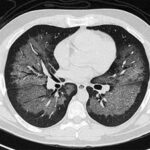

La aspergilosis pulmonar es una infección respiratoria causada por hongos del género Aspergillus, especialmente Aspergillus fumigatus. Este hongo es común...